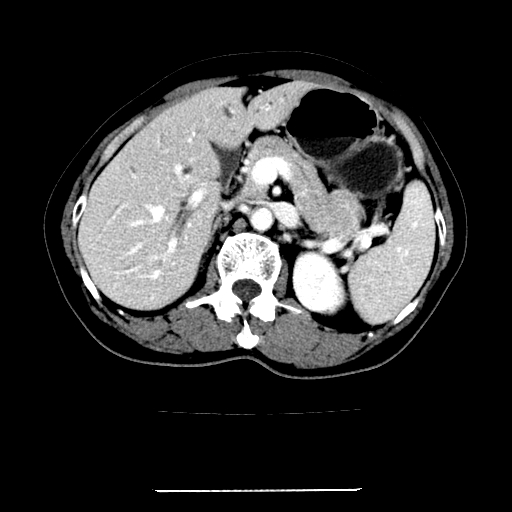

标题: CT22301:女,67岁,上腹部疼痛一周伴皮肤黄染,无发热。 [打印本页]

女,67岁,上腹部疼痛一周伴皮肤黄染,无发热。

左叶肝内胆管结石,并远端肝内胆管扩张。

考虑:肝内胆管结石继发肝内胆管扩张,右肾旋转不良。

肝内外胆管结石并肝内胆管扩张。

建议薄层观察,除外肝门部胆管细胞癌

考虑肝胆管癌;胰头占位?【形态失常,体积增大】

1、肝门高密度影下层面和胰头层面可见轻度胆管扩张,而静脉和延迟期均未见扫描完胰头,不能完全排除胰头占位。2、肝门部高密度影,考虑钙化或结石。

考虑肝门胆管癌伴门脉左支受侵包埋,建议mrcp进一步检查。